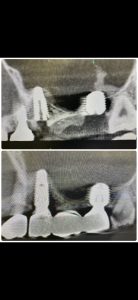

以下の画像は、本日定期検査の方

オペから9ヶ月位の画像、良いね👍👍

デンサーバーでのリフト、採血濃縮血漿板使用

異物の人工骨は一切使わない

目利きある先生方には分かるはず!